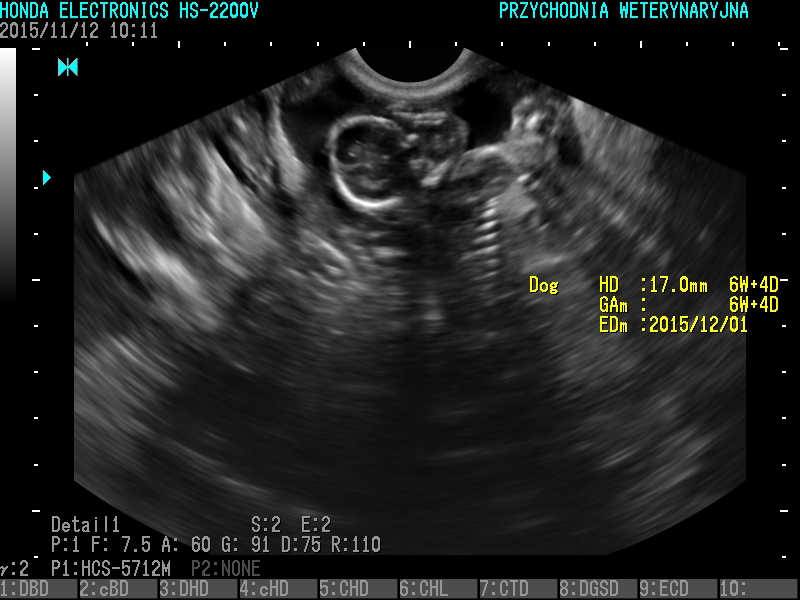

USG

- wykrywanie ciąży, ropomacicza, kamicy moczowej, guzów narządów, wodobrzusza, chorób prostaty, chorób pęcherza moczowego, chorób serca

Badanie USG pozwala na ocenę struktury narządów. Zaletą jest nieinwazyjność, może być wykonywane choćby codziennie. Ważne jest odpowiednie przygotowanie pacjenta do badania- kilkunastogodzinna głodówka i nie oddawanie moczu przez przynajmniej 2 godziny przez badaniem.